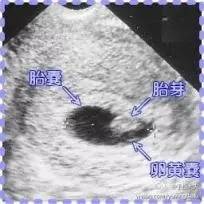

胎芽是什么?在**卵发育过程中,最初两周称为孕卵,以后各器官逐渐形成,经历孕囊—胎芽—胎心,最终形成胎儿。

在**和**结合形成**卵以后,着床**卵慢慢的**成多细胞的孕囊,在怀孕三十多天以后,各原始细胞进行分化,慢慢形成胎芽,胎芽进一步发展形成胎心。这就是一个胎儿形成的过程。

因为胚胎的发育,30—40天形成的是胎囊,40—50天形成的是胎芽,50—60天形成胎心,所以一般的做B超应该是在60天左右的时候做,这时就能够看到胎囊、胎芽、胎心是否正常。